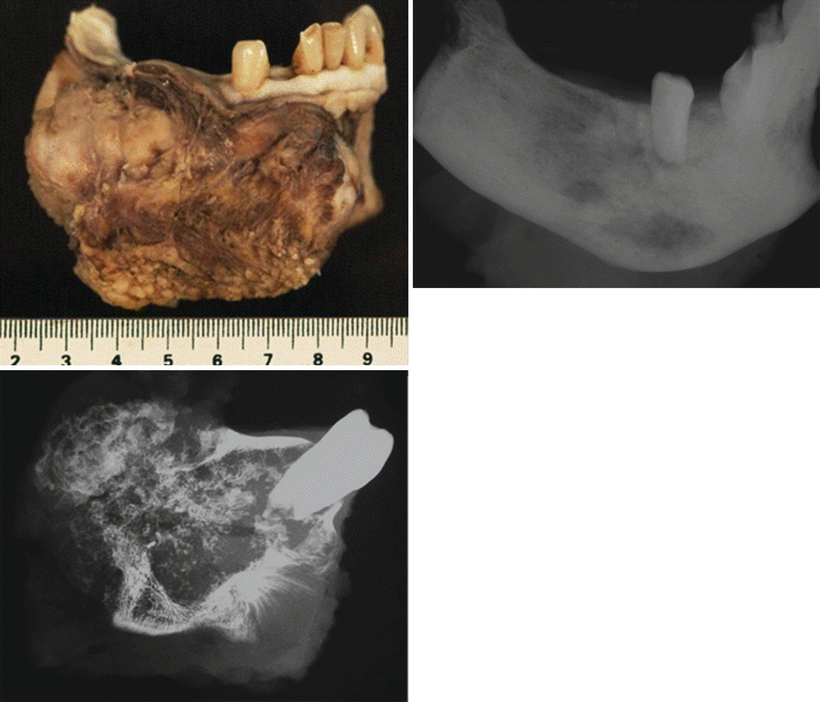

WebAbstract. Although primary bone tumors are relatively uncommon, appropriate imaging evaluation is essential when they are suspected or incidentally detected. In almost all cases, radiographs are the most appropriate initial imaging study for screening and characterization of primary bone tumors.